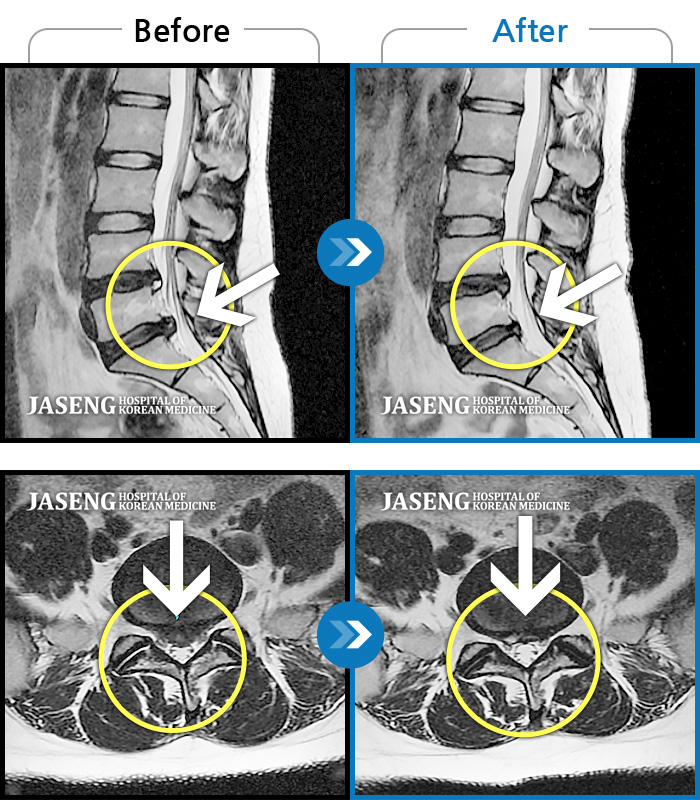

허리디스크

보라매 · 왕오호 원장

허리 통증, 똑바로 서려고 하거나 걸을 때 양쪽 허벅지와 고관절 시큰거림

촬영시기

2017.06.07 ~ 2018.04.17